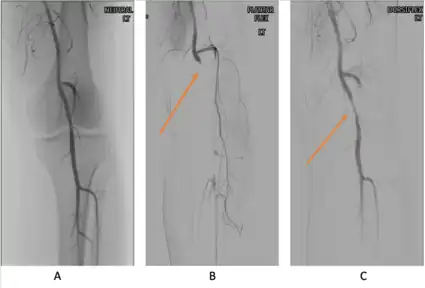

PAES should be suspected in young healthy male patients with clinical symptoms consistent with compression of the vascular structures and without significant cardiovascular risk factors such as smoking.[13] Multiple imaging modalities are used to confirm the diagnosis of PAES.[23] Based on a systemic review by Sinha et al, digital subtraction angiography (DSA) is the most common imaging used for PAES diagnosis, followed by ankle–brachial index (18 percent), computed tomography angiography (CTA) (12 percent), magnetic resonance angiography (MRA) (12 percent), duplex ultrasonography (DU) (10 percent), exercise ankle-brachial index (4 percent), and other modalities (4 percent).[23] According to a recent study by Willimas et al, a combination of DU and MRA is far superior in diagnosing PAES.[24]

Provocative maneuvers can be used to improve visualization of PAES on the imagines.[25] The patient is initially positioned supine with the legs straight, and then instructed to forcefully plantar-flex. A plantarflexion force of 0 to 70 percent maximum has been shown to maximize the sensitivity and specificity for PAES diagnosis.[25] The DU can be a quick, inexpensive, and noninvasive initial screening for PAES. Flow velocities in the popliteal artery will increase, as the popliteal artery is compressed, which is reflected on the DU. If DU is negative but there is still strong suspicion for PAES, MRA or CTA with provocative maneuvers are needed as follow-up imaging. MRA would demonstrate a focal occlusion or narrowing of the mid-popliteal artery, post-stenotic dilatation, or aneurysm of the distal popliteal artery. If MRA or CTA is[13] non-conclusive, DSA may be used as a further option with a high sensitivity (> 97%) for PAES diagnosis.[23]